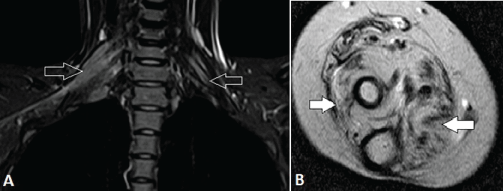

| Figure 11: A 22-year-old female with hereditary motor sensory neuropathy (HMSN). A, Coronal fat-suppressed T2-weighted MR image shows marked asymmetric thickening and disruption of normal internal fascicular architecture of the BP; on the right, from root to cord level and on the left, mildly thickened upper trunk (arrows). B, Axial T2-weighted MR image at the level of right mid forearm shows marked atrophy with fatty replacement (arrows) of the muscles. | ||